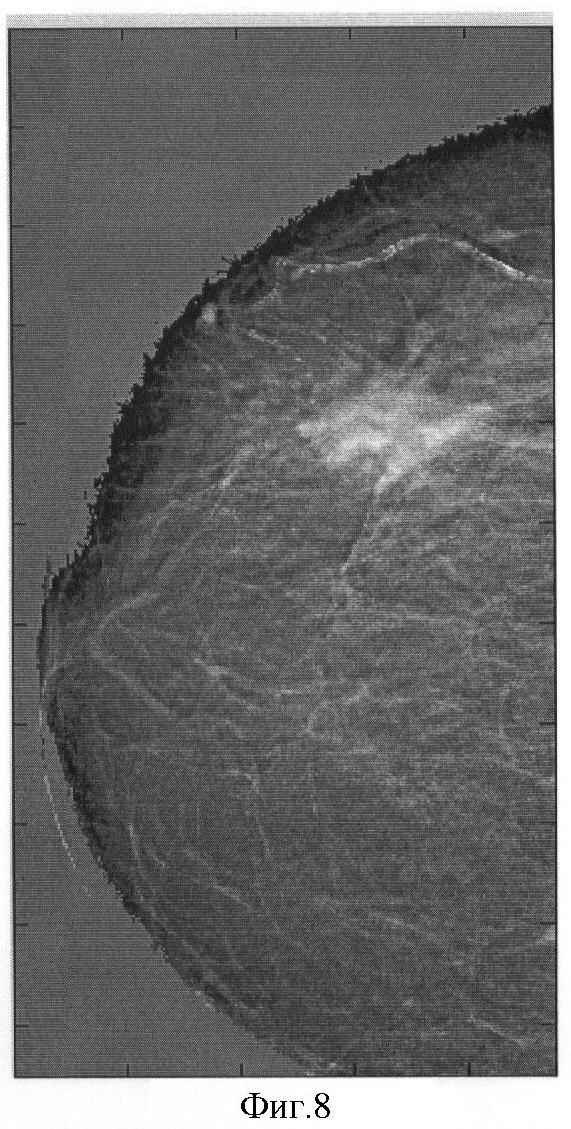

На фиг.1 представлена традиционная молочная железа, на которой прямоугольниками выделены области здоровой ткани (1) и с онкологической тканью (2); на фиг.2 – маммограмма, полученная при использовании способа прототипа; на фиг.3 – зависимость отношения и разности массовых коэффициентов полного поглощения от эффективного атомного номера; на фиг.4 – традиционная маммограмма; на фиг.5 – визуализация распределения эффективного атомного номера; на фиг.6 – традиционная маммограмма (ТМ), эффективный атомный номер (Z), плотность ( ) и их произведение ( Z) онкологической опухоли; на фиг.7 – микрокальцинаты при смещении исходных снимков; на фиг.8 – визуализации распределения идентифицируемого эффективного атомного номера при уменьшении разности энергий излучения; на фиг.9 – визуализации распределения эффективного атомного номера онкологической опухоли при нелинейных преобразованиях исходного распределения числа зарегистрированных фотонов на разной энергии; на фиг.10 – визуализации распределения микрокальцинатов при нелинейных преобразованиях исходного распределения числа зарегистрированных фотонов на разной энергии.

Изменение разности энергий при реконструкции.

Уменьшение разности энергий излучения при реконструкции распределения Z проводит к увеличению чувствительности, к изменению эффективного атомного номера, что делает маммограмму более контрастной (см. фиг.8).